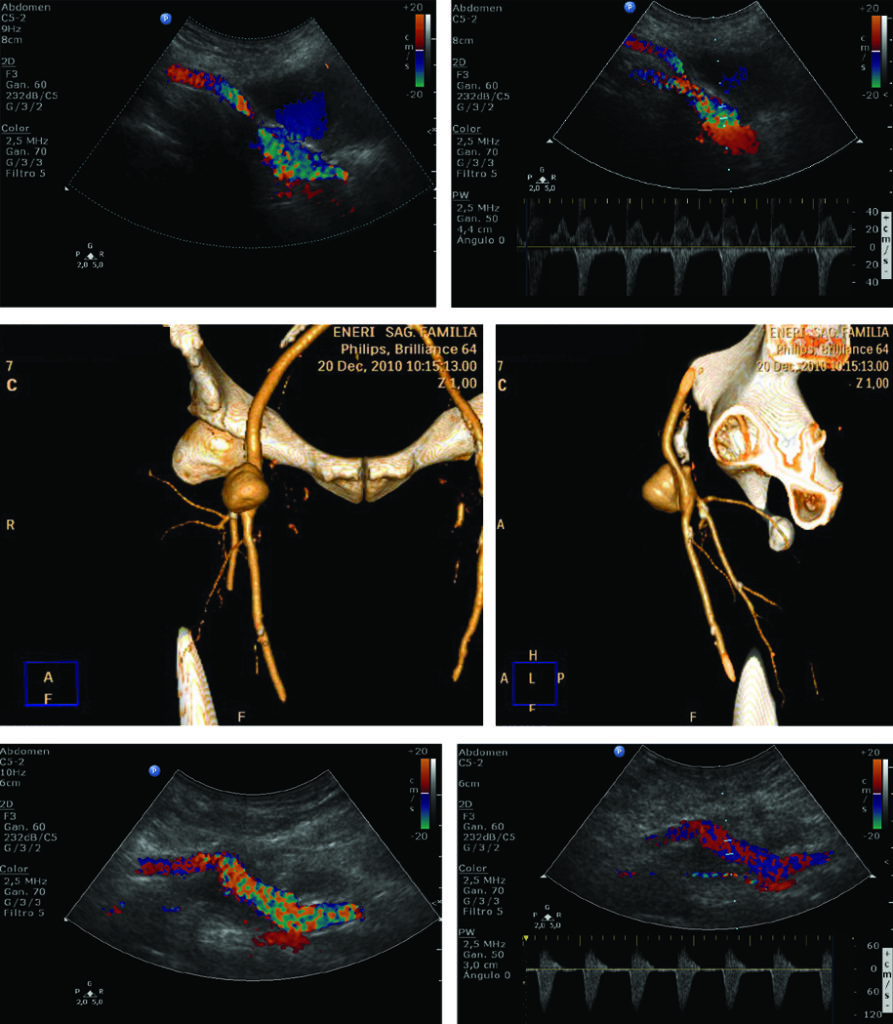

Luego de la visualización de las arterias se realiza, en simultáneo, el análisis espectral de velocidades. Se puede determinar rápidamente la normalidad o la presencia de estenosis a través de la trasformación en el examen del flujo homogéneo laminar y trifásico en un mosaico de colores con el incremento de las velocidades (Fig. 7, Fig. 8, Fig. 9 y Fig. 10). A nivel supra-patelar a cada arteria le corresponde una vena y a nivel infra-patelar, dos venas.

La técnica de evaluación del aneurisma de aorta abdominal incluye mediciones, las cuales deben realizarse desde los bordes externos de la misma. En el plano longitudinal se examina la aorta desde el diafragma hasta la bifurcación ilíaca, y se miden el diámetro anteroposterior y la longitud del aneurisma. En el plano axial se mide el diámetro transverso. Para categorizar el tipo de aneurisma se examina la relación y distancia del aneurisma con respecto a la emergencia de la arteria mesentérica superior, de las renales y de la bifurcación ilíaca. Se examinan las arterias ilíacas y se mide su diámetro para determinar si están comprometidas. Las arterias ilíacas primitivas tienen un diámetro anteroposterior normal de hasta 11 mm (Fig 27).

El DC permite una evaluación más exhaustiva, con la cual no solo podemos determinar con precisión los límites de la dilatación aneurismática sino que también hace posible percibir la turbulencia en el flujo dentro de la misma (Fig. 28).

Luego de la evaluación ultrasonográfica inicial podemos optar por diferentes métodos de diagnóstico por mágenes de manera tal de ampliar el algoritmo diagnóstico y tener una visión más amplia de esta patología. La Angio TC helicoidal, con contraste, es el segundo paso y pre quirúrgico que permitirá no solo realizar una evaluación multiplanar del paciente sino también generar reconstrucciones tridimensionales y así obtener una representación más anatómica de los elementos vasculares (Fig. 31).

Este método de diagnóstico nos permite medir el aneurisma en los planos axial, coronal y sagital, evaluando su cuello y relación con las arterias renales; es indispensable para planear el tratamiento endovascular.